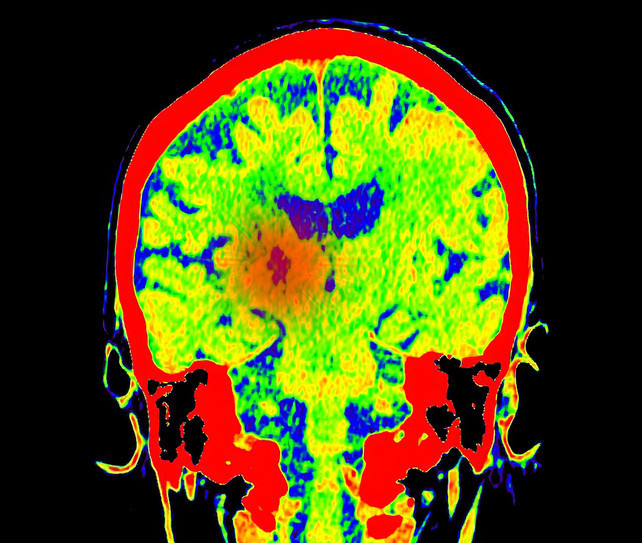

Günümüzde patoloji, sadece mikroskop altında hücre incelemesi yapmanın ötesine geçerek tümörün genetik haritasını çıkarıyor. Yeni nesil dizileme (NGS) gibi moleküler yöntemlerle tümörün DNA'sındaki değişiklikler analiz edilerek; hastalığın seyri öngörülüyor ve doğrudan tümör hücresini hedef alan akıllı ilaçlar seçiliyor.